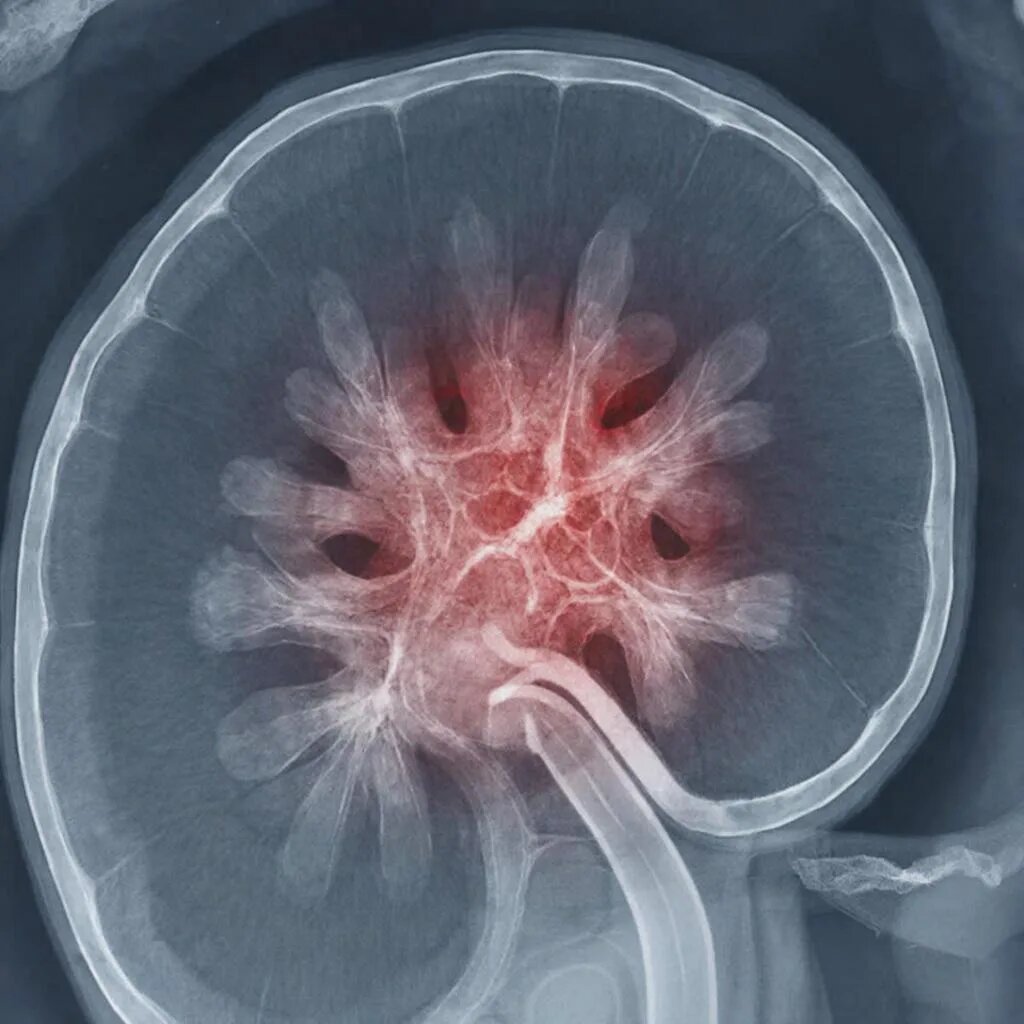

Пять идей для обеда при ХБП: когда запреты не отменяют удовольствия Коллеги, и особенно те, кто столкнулся с необходимостью строгого контроля рациона, я вас прекрасно понимаю. Хроническая болезнь почек (ХБП) — это не просто диагноз, это новый образ жизни, где еда из источника удовольствия часто превращается в источник стресса. «Нельзя соль, нельзя белок, нельзя калий, нельзя фосфор» — от этого списка опускаются руки, и кажется, что в тарелке останется только пресная вареная капуста. Но давайте смотреть правде в глаза: строгая диета будет эффективна только тогда, когда вы сможете ее придерживаться без ежедневного насилия над собой. За долгие годы практики я убедился: если еда безвкусна — пациент срывается. Наша задача — найти баланс между биохимией и гастрономическим удовольствием. Сегодня разберем пять идей для обеда. Это блюда из доступных продуктов, которые легко приготовить и которые не навредят вашим почкам, если вы знаете меру и свои показатели. Важное предисловие: Стадия ХБП у вс